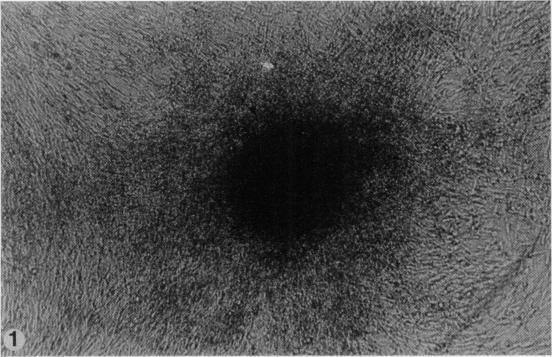

SPECIFIC COMPLEMENT-FIXING ANTIGENS IN POLYOMA TUMORS AND TRANSFORMED CELLS.

Virology. 1965 Jan;25:55-61. doi: 10.1016/0042-6822(65)90251-5.